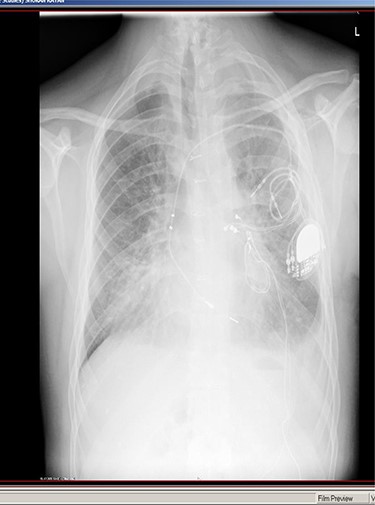

A 31-year-old male with Down’s syndrome presented with repeated hospital admissions over the previous year complaining of upper abdominal pain, nausea, postprandial vomiting and 10 kg weight loss. In 2004, he had undergone a previous laparoscopic repair of a Morgagni hernia with mesh insertion at our institution but was lost to follow-up. Past medical history included a Ventricular septal defect (VSD) repair, Atrioventricular (AV) block with pacemaker insertion and hypothyroidism. A chest X-ray (Fig. 1) showed right middle lobe consolidation, and a thoracoabdominal CT demonstrated the mesh located in the anterior thorax, which contained colon without any features of ischemia (Fig. 2). Gastroscopy and colonoscopy were normal.